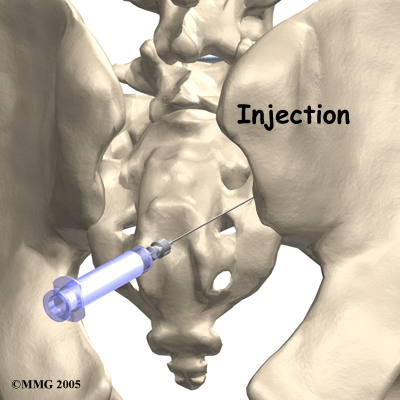

If conservative treatment is unsuccessful, your doctor may suggest injections to the joint. As described above, injections are used primarily to confirm that the pain is coming from the SI joint but they can also be useful in controlling the pain. A series of cortisone injections may be recommended to try to reduce the inflammation in and around the SI joint. Cortisone is a powerful anti-inflammatory medication that is commonly used to control pain from arthritis and inflammation. Other medications have been injected into the joint as well. A chemical called hyaluronic acid has been used for years to treat osteoarthritis of the knee. This chemical is thought to reduce pain due to its lubricating qualities and its ability to nourish the articular cartilage in the synovial joints. The true mechanism of action remains unknown, but it has been used with some success in the SI joint. All of these injections, unfortunately, are temporary and are expected to last several months at the most.

Another procedure that has been somewhat successful for chronic SI joint pain is called radiofrequency ablation. After a diagnostic injection has confirmed that the pain is coming from the SI joint, the small nerves that provide sensation to the joint can be "burned" with a special needle called a radiofrequency probe. In theory, this destroys any sensation coming from the joint, making the joint essentially numb. Unfortunately this procedure is not always successful. If it does help, it is temporary but can last for up to two years and can be repeated if needed.